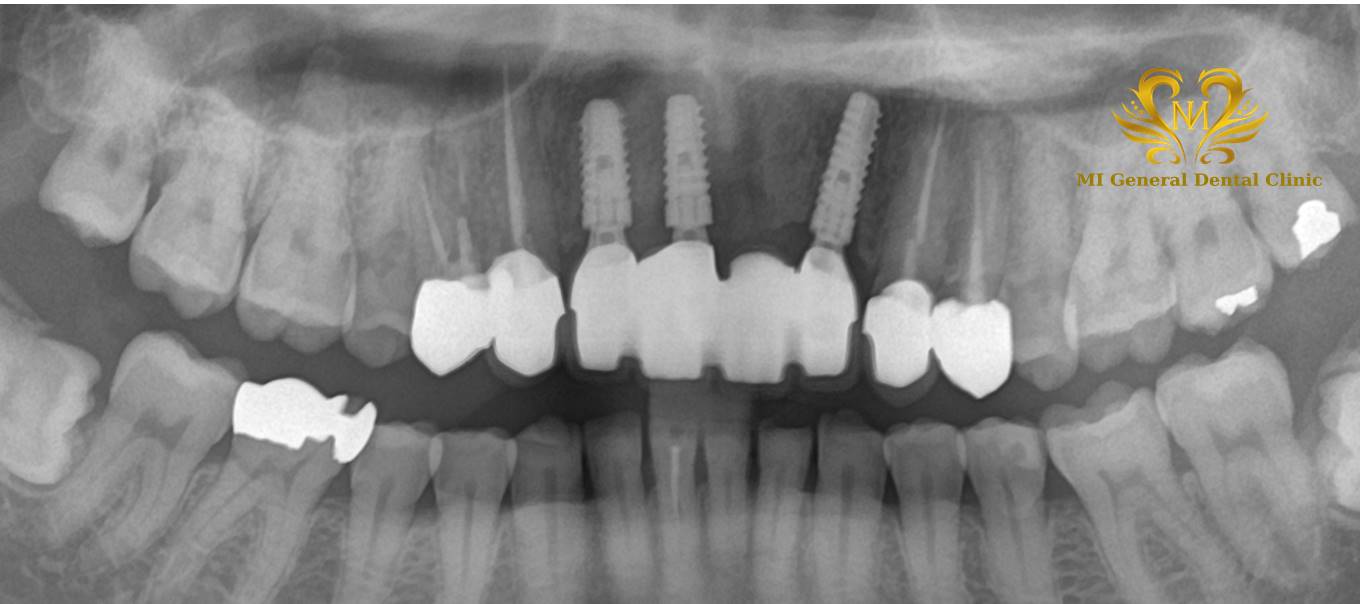

前歯の多数歯欠損のインプラント症例

前歯が複数なく長いブリッジが入っていましたが、支えている歯が痛み出したためブリッジの除去ならびに欠損部分のインプラント治療を行う事としました。

治療後

残せる周りの天然歯は根管治療を行い、前歯はインプラント治療を行いました。機能的にも審美的にも綺麗な前歯が入りました。

| 主訴 | 前歯のブリッジの支えが痛い。負担をなくしたい。前歯で噛みたい。 |

| 治療内容 | 前歯のブリッジの支えが痛くなり来院。ブリッジを除去し、仮歯に置き換えて根管治療。その後、前歯4本欠損のインプラント治療及び骨造成。その後、仮歯の調整等をしてセラミックスのインプラント上部構造装着。 |

| 治療期間 | 10ヶ月 |

| 治療費 | 144万円+消費税 |

| 治療で得られるメリット | インプラント治療をすることで長いブリッジによる周囲の歯の負担軽減。しっかり噛めるよになりました。見た目も綺麗になりました。 |